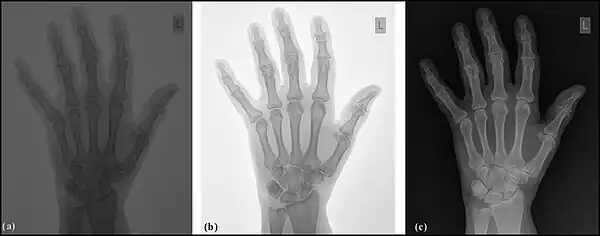

Image sampling is the process used to digitise the spatial information in an image. It is typically achieved by dividing an image into a square or rectangular array of sampling points - see the following figure. Each of the sampling points is referred to as a picture element - or pixel to use computer jargon. Although in the context of DR image receptors, the term detector element, or del, is also used. Naturally, the larger the number of pixels or dels, the closer the spatial resolution of the digitised image approximates that of the radiation pattern transmitted through the patient – see the following figure, panels (a) and (b).

Note that each pixel represents not a point in the image but rather an element of a discrete matrix. Distance along the horizontal and vertical axes is no longer continuous, but instead proceeds in discrete steps, each given by the pixel size. With larger pixels, not only is the spatial resolution poor, since there is no detail displayed within a pixel, but grey-level discontinuities also appear at the pixel boundaries (pixelation) - see panel (b) in the figure. The spatial resolution improves with smaller pixels and a perceived lack of pixelation gives the impression of a spatially continuous image to the viewer.

Image quantisation is the process used to digitise the brightness information in an image. It is typically achieved by representing the brightness of a pixel by an integer whose value is proportional to the brightness. This integer is referred to as a 'pixel value' and the range of possible pixel values which a system can handle is referred to as the grey scale. Naturally, the greater the grey scale, the closer the brightness information in the digitised image approximates that of the original image – see the following figure, panels (a) and (c). The process can be considered as the digitisation of image brightness into G shades of grey. The value of G is dependent on the binary nature of the information coding. Thus G is generally an integer power of 2, i.e. G=2m, where m is an integer which specifies the number of bits required for storage. Examples of values of G are 1,024 (m=10) in fluoroscopy, 2,048 (m=11) in angiography and 4,096 (m=12) in digital radiography. Note that the slight difference between the brightness in an analogue image and its pixel value in the digital image is referred to as the quantisation error, and is lower at larger values of G.